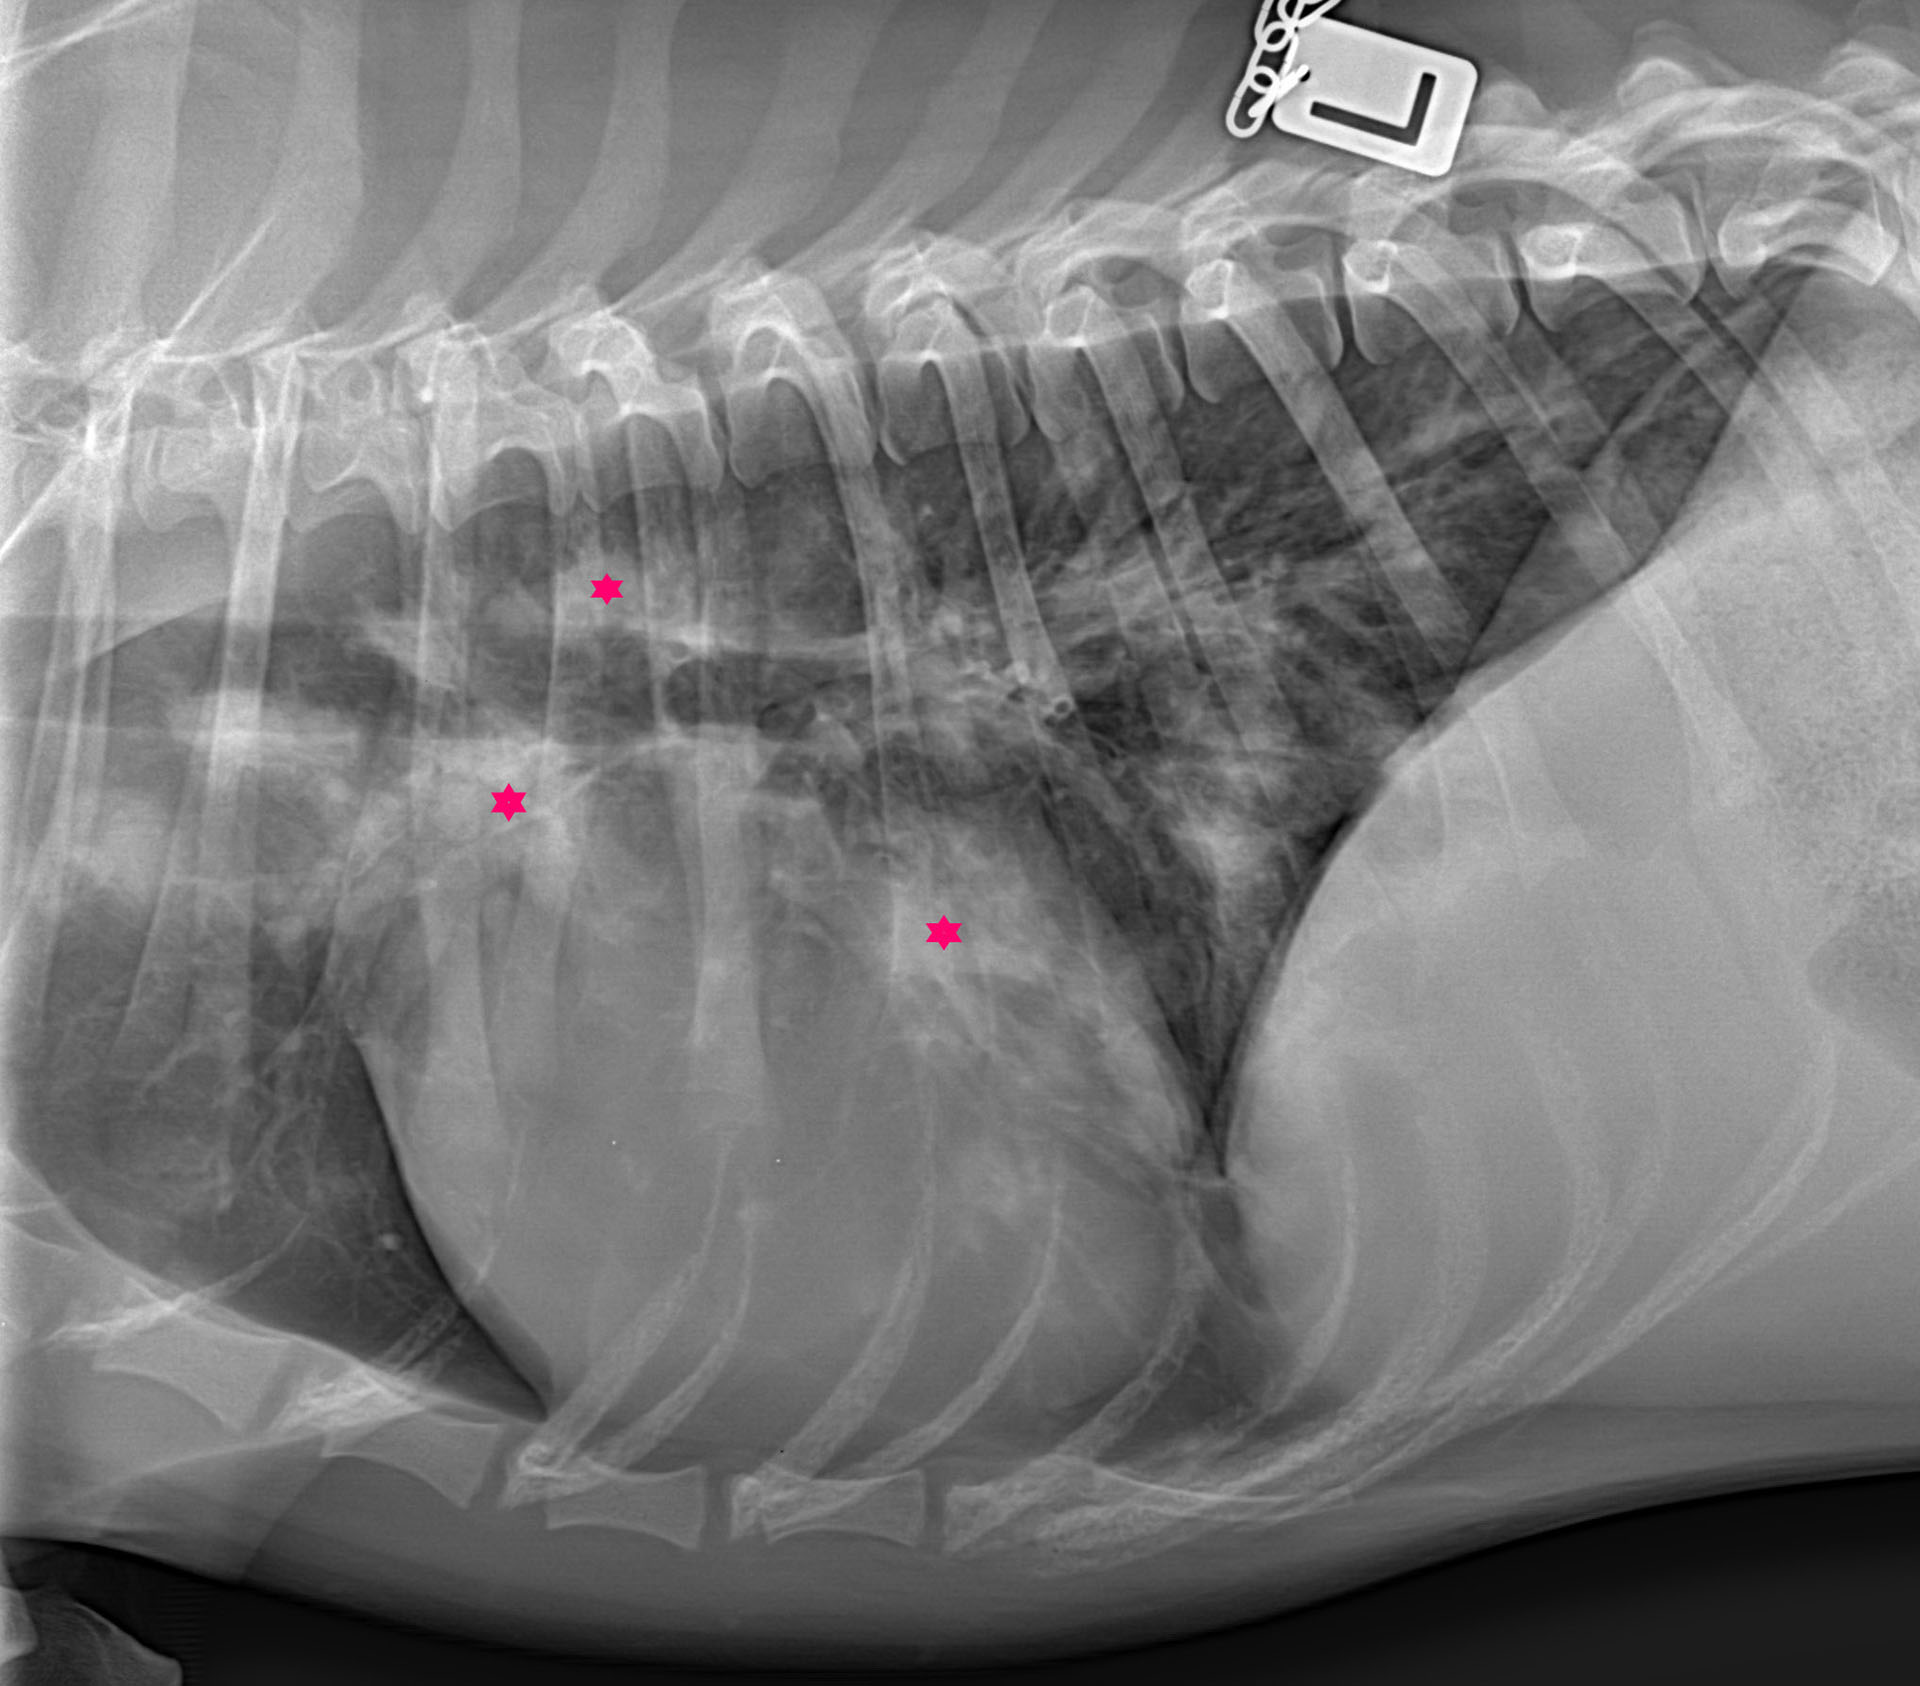

Figur 4. Røntgen av thorax i venstre sideplan. Tydelig multifokale opasiteter (røde stjerner) i dorsokraniale og ventrokaudale lungefelt.

Foto: Empet Halden Dyreklinikk

Det ble sett fokale, flekkete fortetninger diffust fordelt dorsokranialt i lungefeltet i venstre sideplan (Figur 4), samt perihilært i området for de bronkiale lymfeknutene.

Det er sannsynlig at pasientenes lymfadenitt var immunmediert basert på den nødvendige og langvarige behandlingen med kortison, og mangelfulle responsen på antibiotika. Tilstanden steril steroidresponsiv lymfadenitt beskrevet spesielt hos engelsk springer spaniel er antatt å forekomme til dels som følge av en type IV immunopatologisk reaksjon. Reaksjonen kjennetegnes av en cellemediert immunrespons der vedvarende T-celle og makrofag-stimulering forårsaker nøytrofil eller pyogranulomatøs inflammasjon spesielt i lymfeknuter, lunger og hud som respons på kronisk antigenstimulering (8,9). Det er derfor nærliggende å anta at en liknende mekanisme forårsaket lymfadenitt i disse pasientene. En annen mulig mekanisme for utvikling av sekundær lymfadenitt i disse hundene er type II immunopatologiske reaksjoner (10) som ses ved immunmediert hemolytisk anemi (IMHA), steroidresponsiv meningitt-arteritt (SRMA), immunmediert polyartritt (IMPA) og immunmediert trombocytopeni (ITP). Denne typen kjennetegnes av komplementfiksering og aktivering av NK-celler og andre fagocytterende celler, stimulert av celle-assosierte antigener eller celleoverflateantigener. De viktigste immunoglobulinene i type II reaksjoner er IgG og IgM (11). Både type II og type IV-immunopatologiske reaksjoner krever immunsuppressiv og/eller immunmodulerende behandling. Begge hundene i disse kasuistikkene hadde lokal mesenteriell lymfadenopati uten affeksjon av viscerale eller perifere lymfeknuter som kunne reflektere en respons på peroralt inntak av bakterien. Hunden i Kasuistikk 2 hadde også patologiske forandringer i thorax, som kunne indikere kombinert peroral- og inhalasjonssmitte hos denne hunden.